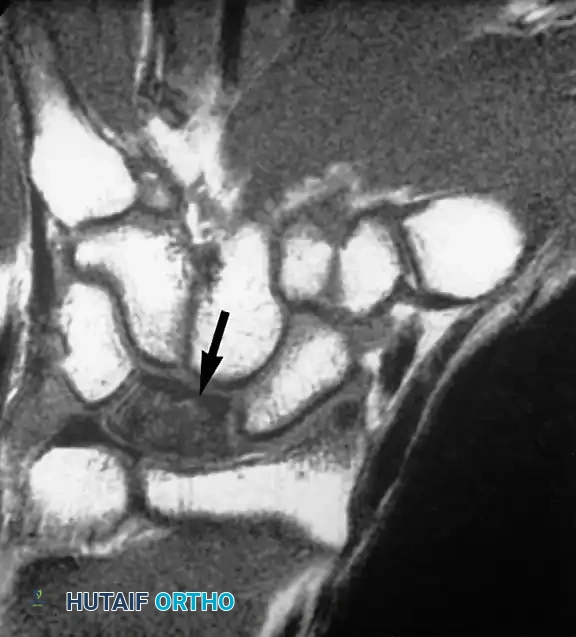

تنخر العظام في المعصم

تعتبر حالات مثل مرض كينبوك (تنخر العظم الهلالي) وتنخر العظم الزورقي (الذي يحدث غالباً بعد الكسور) من الحالات التي يبرع الرنين المغناطيسي في تشخيصها مبكراً. يشير فقدان الإشارة الطبيعية لدهون نخاع العظم في صور الرنين إلى نقص التروية الدموية وموت الخلايا العظمية.

تنخر العظم الهلالي في المعصم أو ما يعرف بمرض كينبوك كما يظهر في الرنين المغناطيسي

تنخر العظم الزورقي بعد التعرض لكسر في اليد